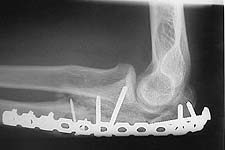

The olecranon is certainly comminuted, but if the wound is small all the pieces should be there. I would favor an attempt at ORIF w/ plating to reconstruct as much as possible. He is a young laborer and should have good bone quality.

The attached case was similar, but not quite as comminuted.

3 months post-op: